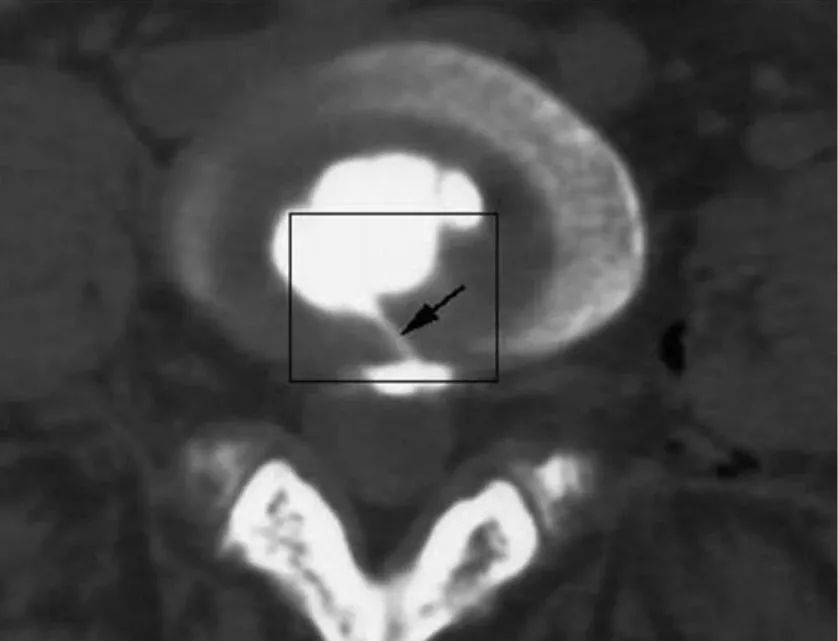

4.腰椎间盘造影是一种有创性的检查椎间盘源性腰痛患者的方法,诊断依据包括目标椎间盘注射时发生疼痛,而相邻椎间盘注射无疼痛或疼痛轻微。其他的标准包括低压力或低容量注射时疼痛重现,同时伴有椎间盘形态异常改变。

椎间盘造影后CT平扫所显示破裂的纤维环,且造影剂流经至 HIZ 高信号区,提示椎间盘源性腰痛的诊断。